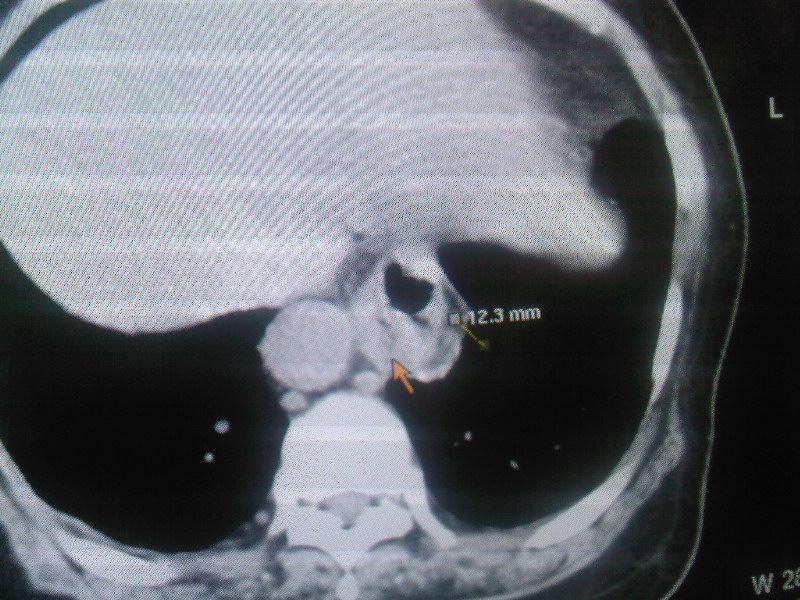

食管下段近贲门处可见前方一限局性空腔影。想临食管避受压,且与食管分界不清,跨与食管裂孔处,顶部位于中后纵膈,请指教

食管癌,与下面连起来,就好判断了.

食管壁不规则增厚,年龄大考虑为占位肿瘤性病变

食管下段占位性病变,建议食管钡透检查。